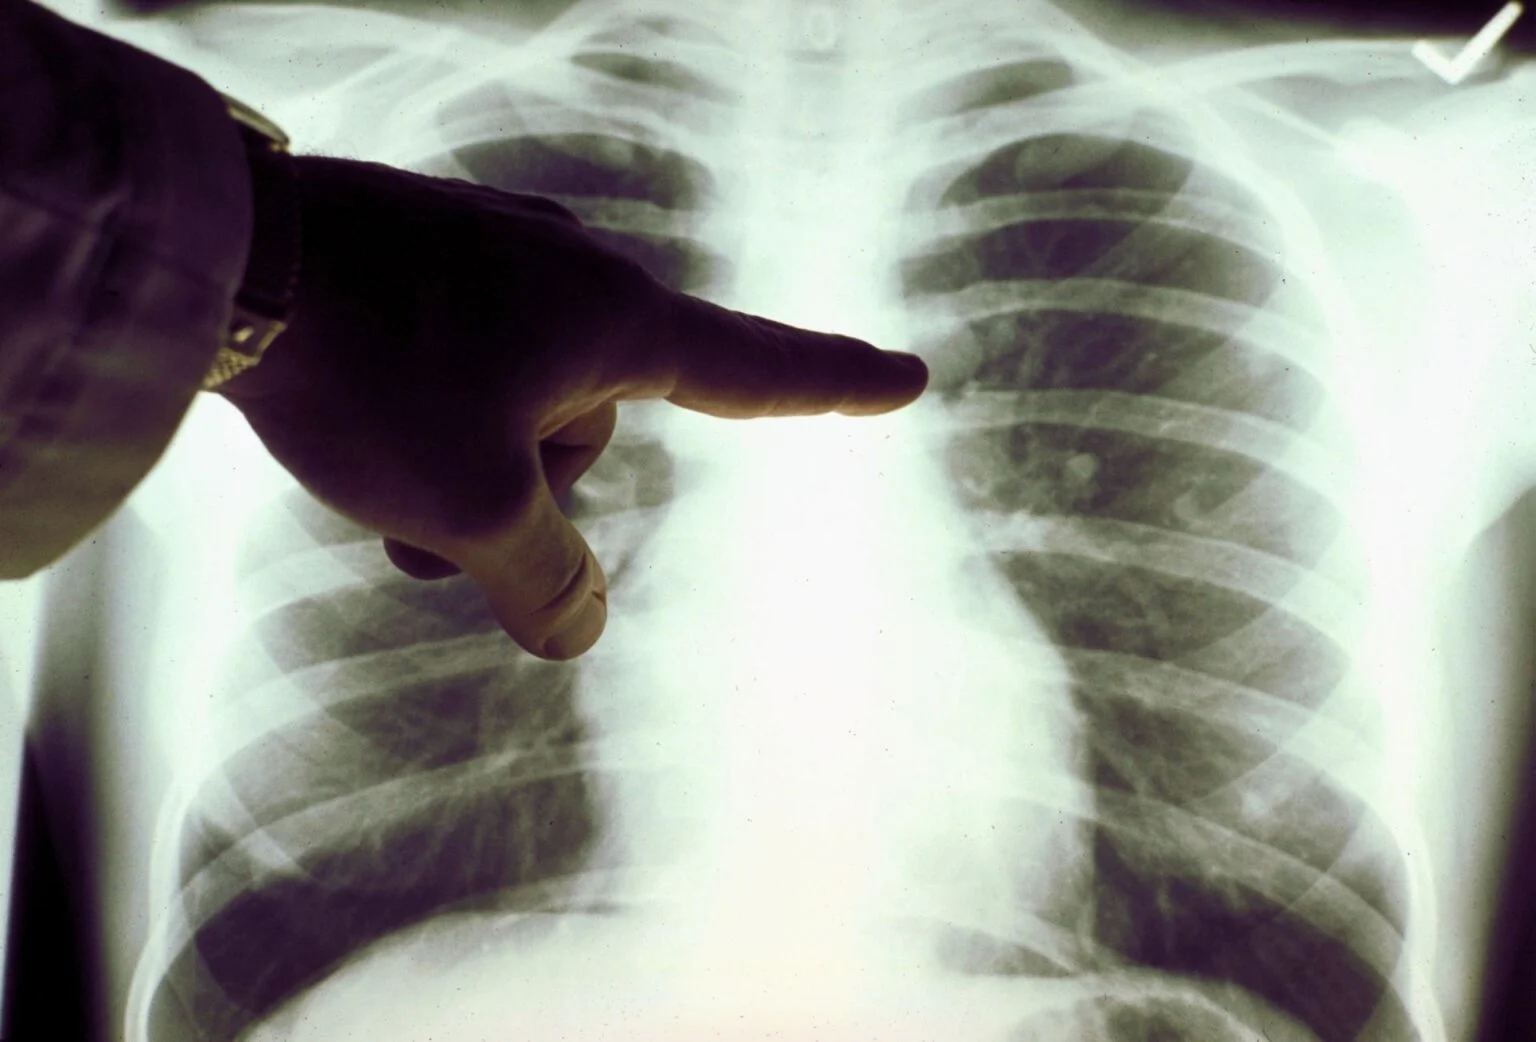

Καρκίνος του πνεύμονα: Πρόκειται για ένα συνηθισμένος και θανατηφόρο καρκίνο. Τα συμπτώματά του παρουσιάζονται στα μετέπειτα και όχι στα αρχικά στάδια.

Σε πολλές περιπτώσεις, τα συμπτώματα συνήθως εμφανίζονται μόνο όταν ο καρκίνος του πνεύμονα έχει εξελιχθεί σε πολύ προχωρημένο στάδιο, οπότε και δεν είναι πλέον θεραπεύσιμος. Όπως και πολλοί άλλοι καρκίνοι, ο καρκίνος του πνεύμονα μπορεί να ανιχνευθεί στο αρχικό στάδιο (στάδιο 1), οπότε είναι σημαντικό να αναγνωρίσουμε όλα τα συμπτώματα.